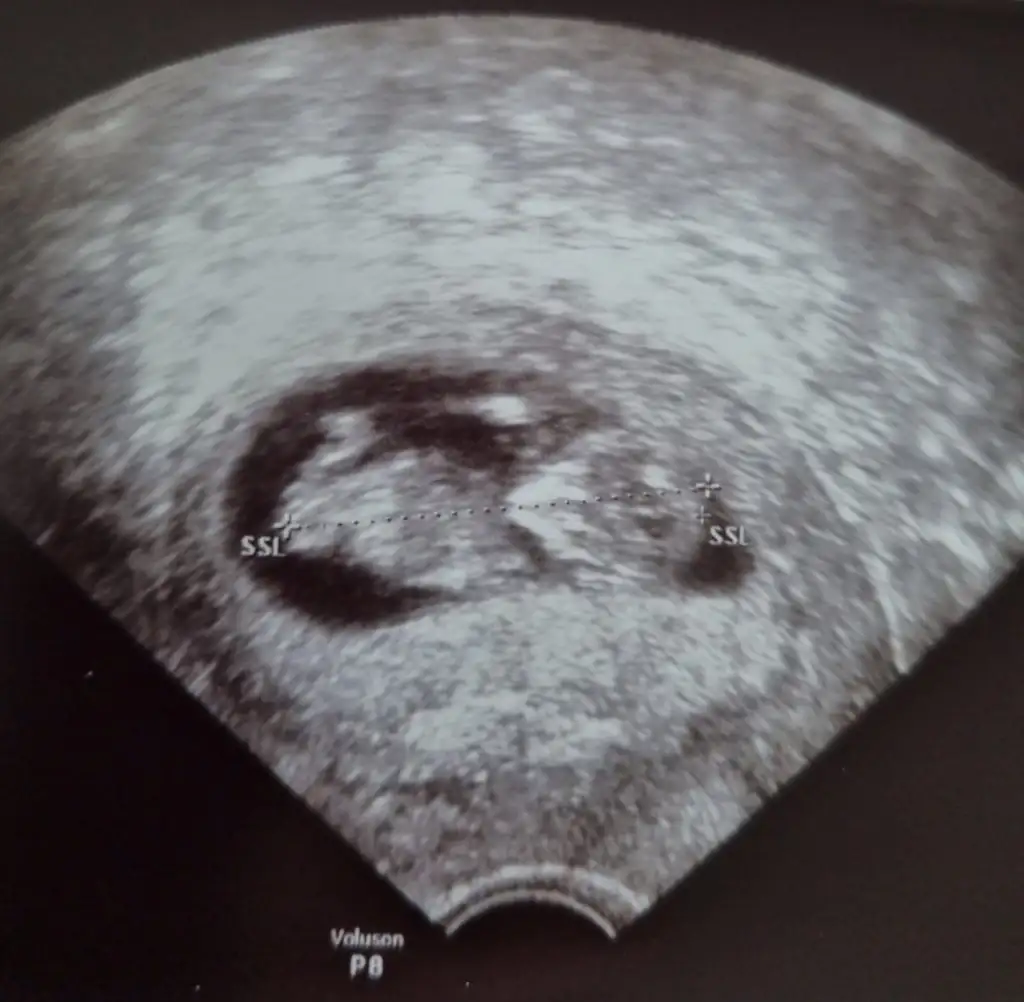

Nubu dik görünüyor du sağlıkla gelsin bebeğinizMerhaba benimde kesinleşti siz erkek demiştiniz doktor kız dedi kesinleşti

TeşekkürlerNubu dik görünüyor du sağlıkla gelsin bebeğiniz![]()

Erkek gibi sanki diğeri net değil USG biri erkek gibi görünüyorMerhaba bizede cinsiyet tahmini yapabilir misin canimIkra meyra